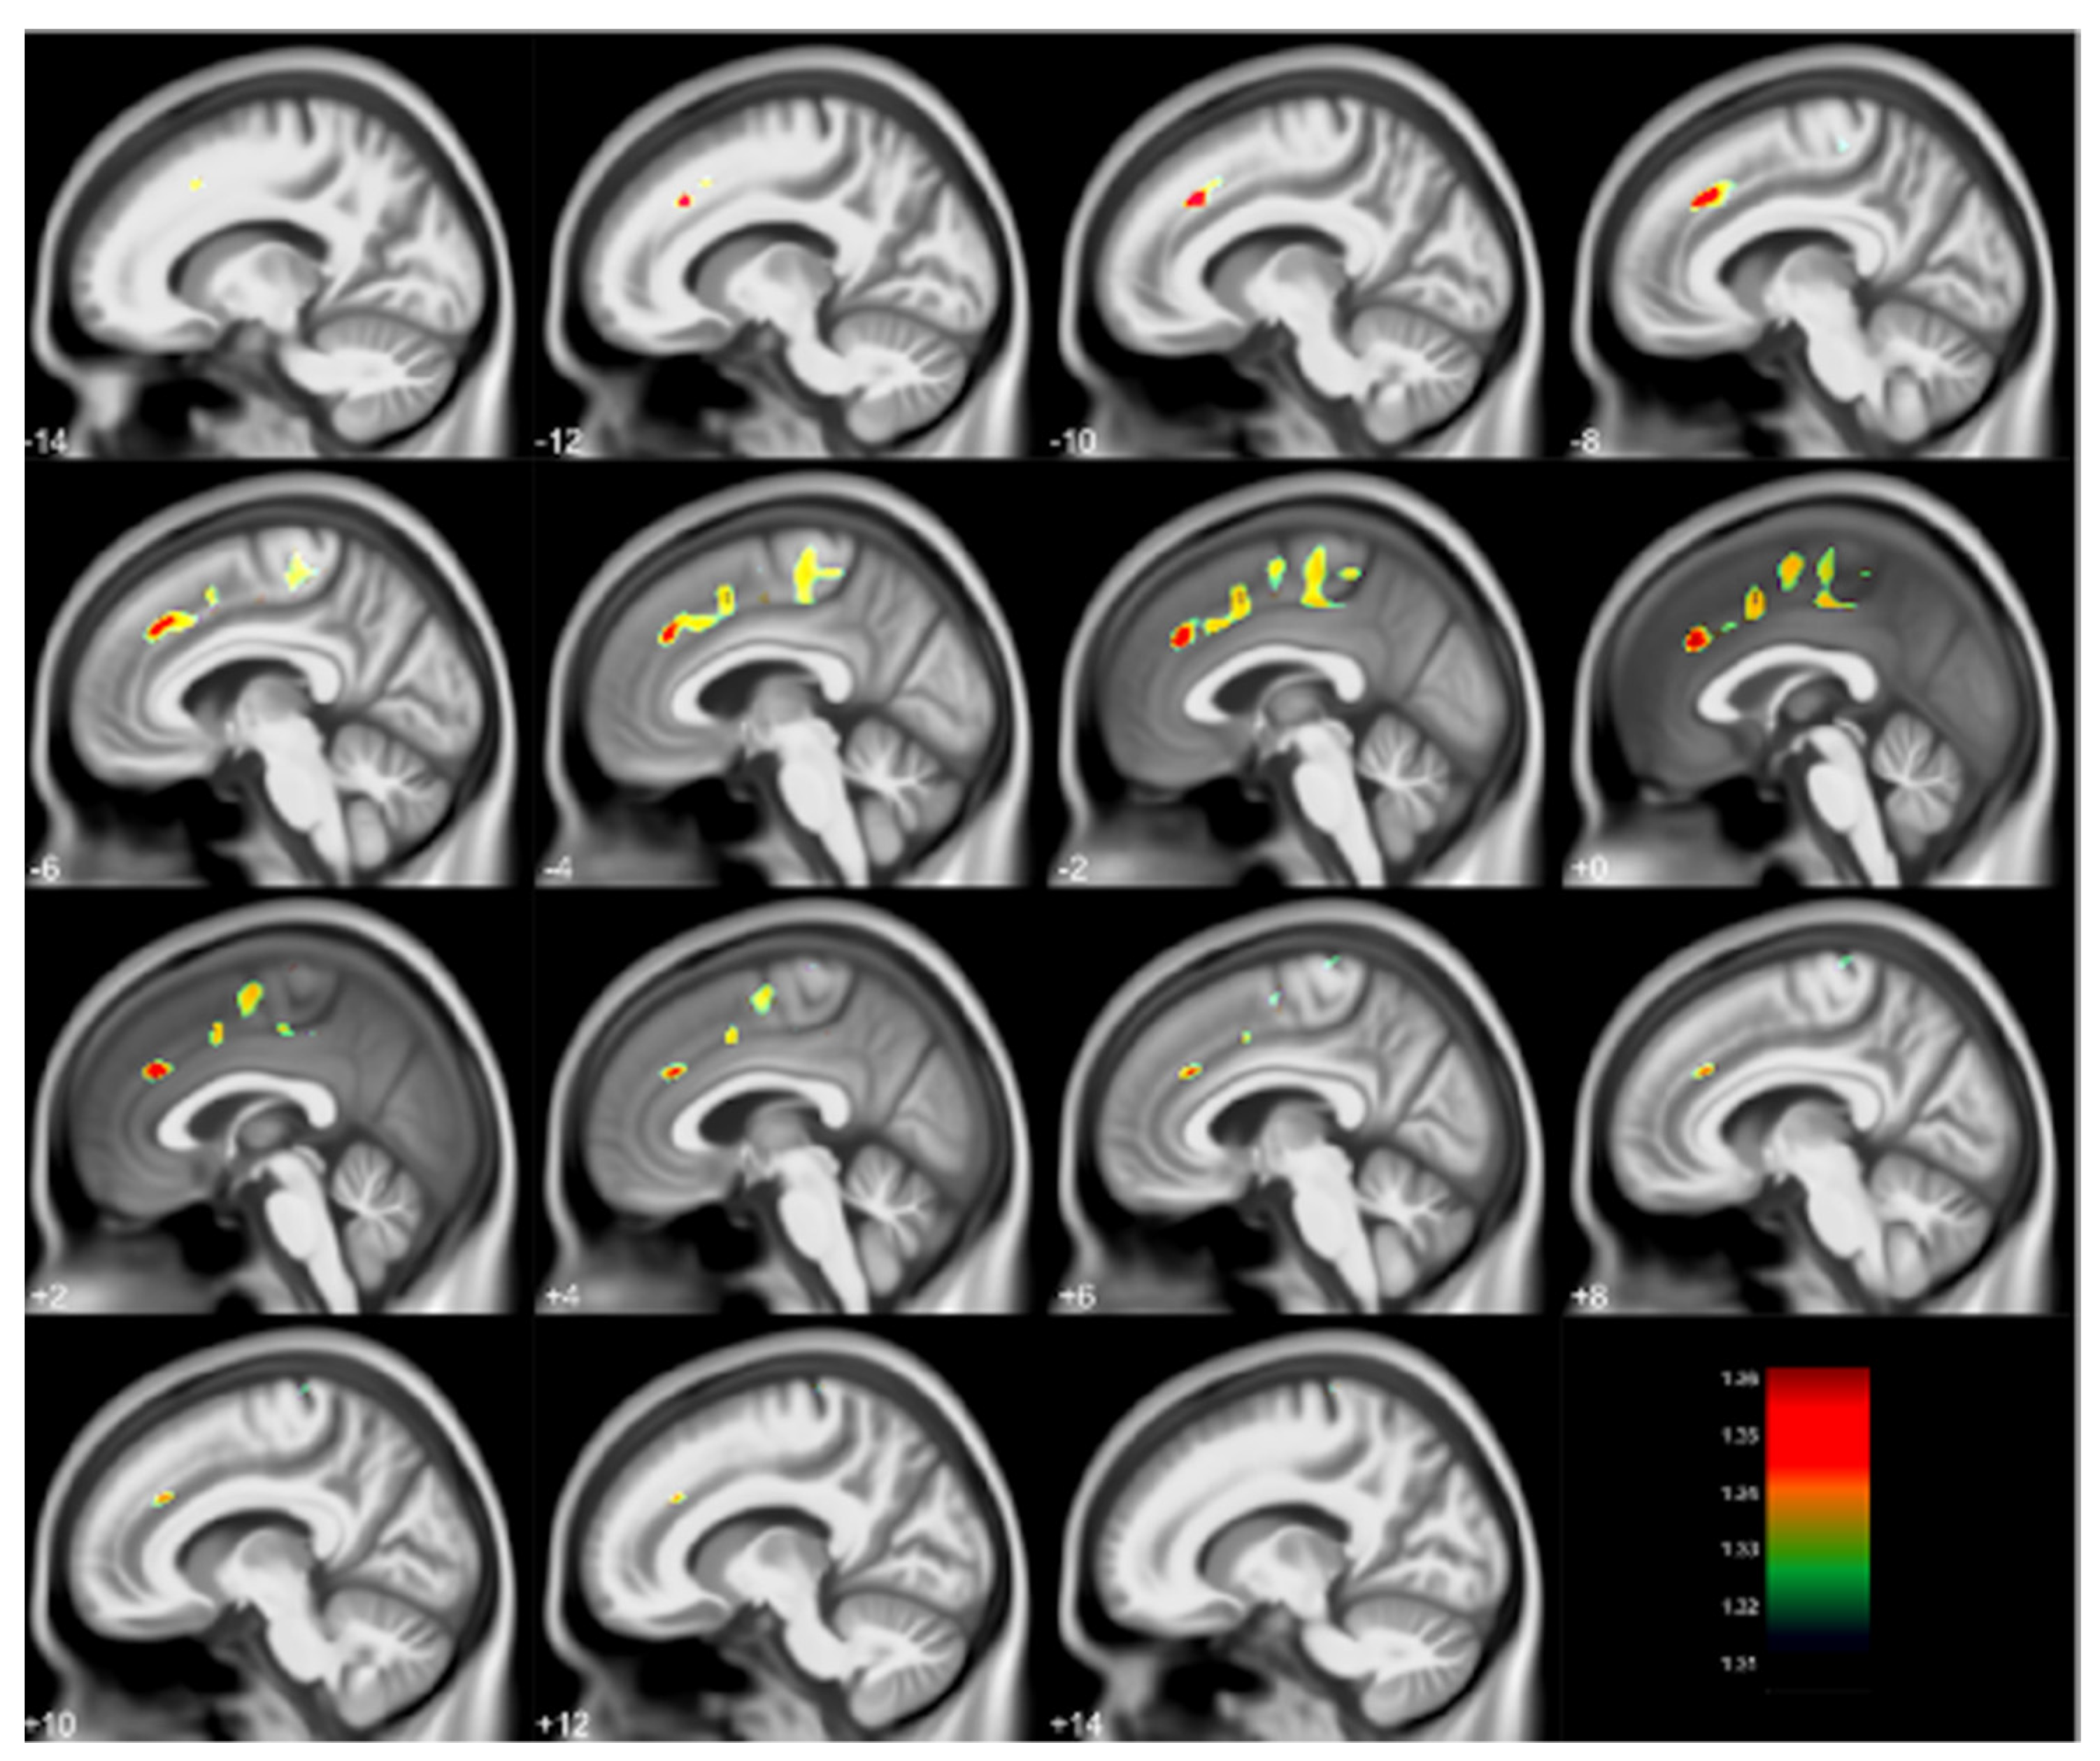

- Cecil, K.M.; Dietrich, K.N.; Altaye, M.; Egelhoff, J.C.; Lindquist, D.M.; Brubaker, C.J.; Lanphear, B.P. Proton magnetic resonance spectroscopy in adults with childhood lead exposure. Environ. Health Perspect. 2011, 119, 403–408. [Google Scholar] [CrossRef] [Green Version]

| Childhood Blood | MRS | Adult | Reduced metabolite concentrations | Cecil et al. [10] |